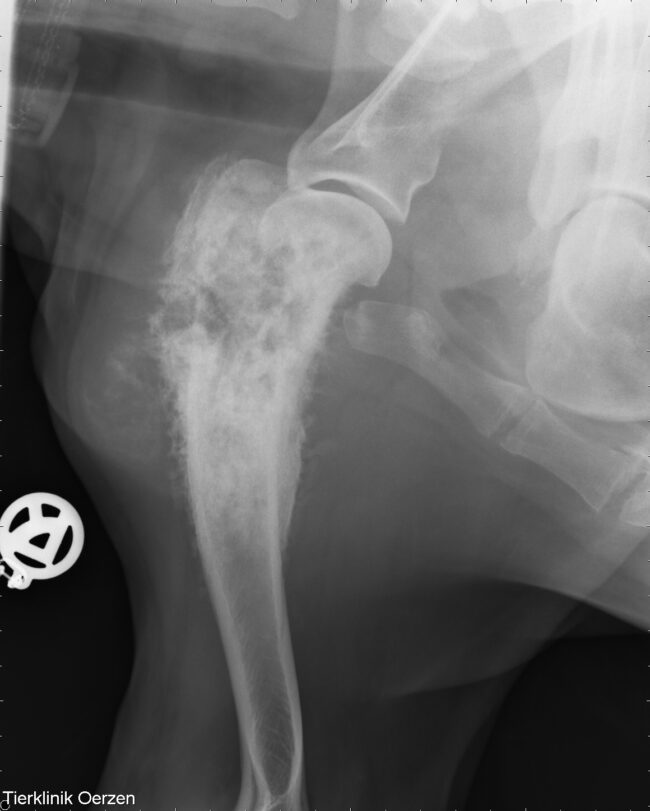

Osteosarkom beim Hund

Das Osteosarkom ist die glaub ich am häufigsten Krebserkrankung die es mittlerweile gibt. Wir haben schon viele Patienten mit Osteosarkom betreut, manche wurden noch amputiert und bei anderen war es so weit Fortgeschritten das man nicht mehr amputieren konnte. Das Osteosarkom ist ein primärer Knochentumor, das heißt der Tumor entsteht im Knochen, metastasiert aber nicht…